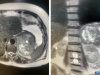

В преддверии Нового года врачи-онкологи миасской Городской больницы № 2 провели уникальную операцию 64-летней пациентке, удалив 8-сантиметровую опухоль, которая распространялась в забрюшинное пространство и произрастала из стенки желудка. Подобные случаи встречаются крайне редко - около 10-15 случаев на миллион человек, отметили в пресс-службе медицинского учреждения.

Дополнительные исследования, включая МРТ и ФГС, показали, что опухоль не затрагивает просвет желудка, а располагается на его наружной стенке. Это позволило врачам предположить, что пациентка столкнулась с редкой формой саркомы желудка, требующей незамедлительного хирургического вмешательства.

Операция, которую провели заместитель главного врача Алексей Зайков и врач-онколог Геннадий Калашников, длилась полтора часа. Опухоль находилась между жизненно важными органами: желудком, поджелудочной железой, селезенкой, почкой, надпочечником и аортой. Она также инвазировала в диафрагму, что потребовало её частичной резекции. Врачам удалось полностью освободить опухоль и удалить её вместе с частью стенки желудка, не вскрывая органа.

"Это кистозно-солидная опухоль забрюшинного пространства, она имеет в своем составе тканевой компонент и жидкость. Такое новообразование нельзя верифицировать, невозможно взять биопсию до удаления. Скорее всего, это агрессивная форма саркомы, медлить с операцией было нельзя", - рассказал заместитель главного врача по медицинской части, врач-онколог Алексей Зайков.